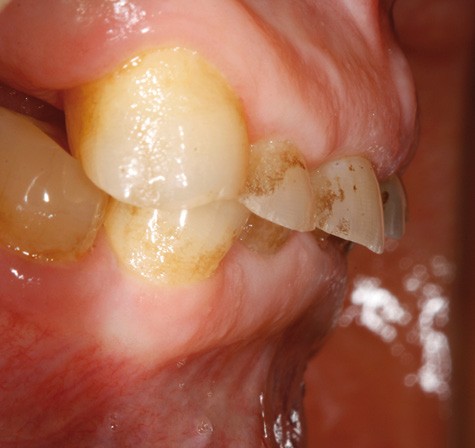

Examen clinique (fig. 1-6)

• L’examen intrabuccal montre de nombreux édentements non compensés (14, 15, 16, 24, 25, 26, 27, 47 et 36) ainsi que des pertes de substance très importantes, notamment dans le secteur antérieur.

Une attrition sévère, couplée à une occlusion sans calage postérieur, a engendré des difficultés pour s’alimenter.

La perte de dimension verticale par usure prématurée nécessite d’augmenter cette dernière de façon importante, et en une seule fois.